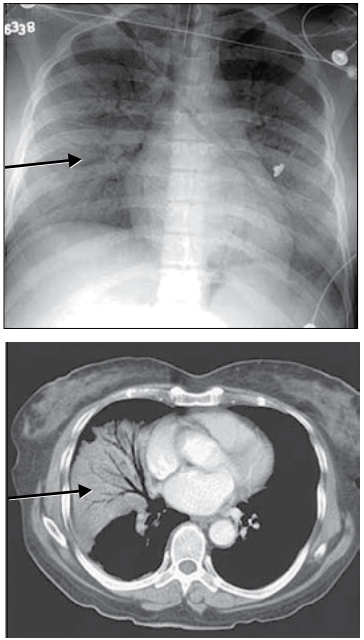

Analise as imagens.

(Arquivo pessoal; imagens usadas com autorização)

Qual é o achado radiológico indicado pelas setas nessas imagens?